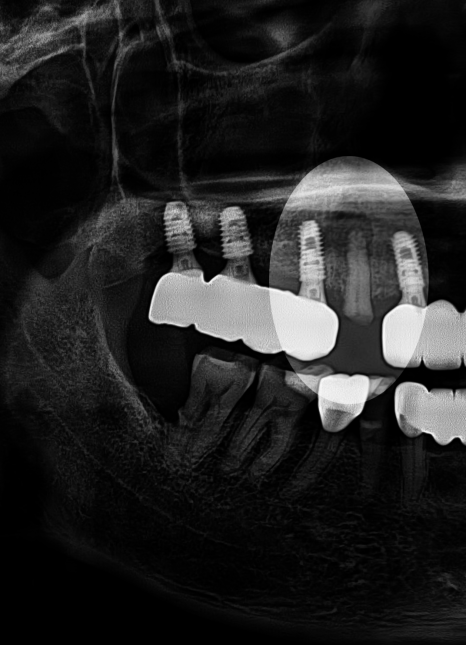

사진을 보시면 우측 윗쪽 앞니의

머리 부분이 온전히 부러졌습니다.

단순히 눈으로 보거나 기구로 만져 반응을 평가하는 것만으로

어떤 상태인지 평가하긴 어렵습니다.

그래서 Panorama나 CBCT 같은 자료를 통해

내부 상태를 확인하게 됩니다.

당산동 치과 에서 준비한 사진을 보시면

안쪽 신경이 외부로 드러난 것을 확인할 수 있습니다.

파절 범위가 넓어 치수까지 침범했는데,

아직까지 염증 반응은 없었습니다.

만약 신경 손상이 심하거나 광범위한 영역에

염증이 만들어졌더라면 발치까지 고려되었을 텐데

아직 자연치 보존이 가능하다 판단되어

신경치료를 통해 개선 가능하다 판단됩니다.